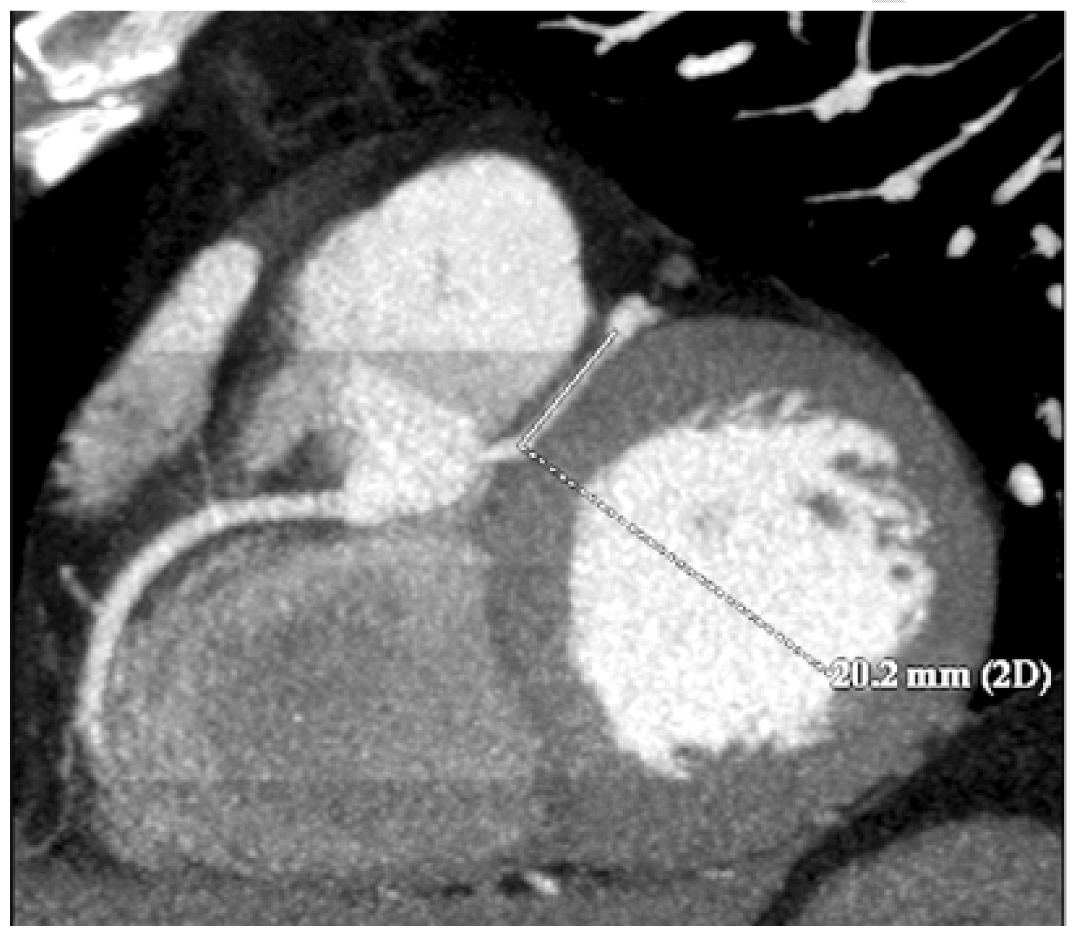

A 45-year-old male was admitted in our department with symptoms characterized by intermittent substernal chest discomfort non-provoked by exertion or emotional stress enlarging for over four months. The patient was a smoker of 7–8 packs of cigarettes per week for 10 years. Clinical history was negative for hypertension, diabetes mellitus, hyperlipidemia or family history of premature vascular disease and no risk factors for pulmonary embolism or respiratory distress. Physical examination showed normal blood pressure (BP: 128/88 mmHg), heart rate of 73 beats/min, no signs of vascular disease and normal cardiac examination. Initial laboratory tests showed no particular anomalies with normal blood levels of glucose and cholesterol (LDL: 103 mg/dl; HDL: 35 mg/dl; TG: 198 mg/dl). Resting electrocardiogram (ECG) showed normal sinus rhythm at 82 beats/min without anomalies in stress examination. Several echocardiographic examinations revealed a moderate enlargement of the left atrium; an apical form of left ventricular hypertrophy; a preserved left ventricular (LV) systolic function (LV ejection fraction, 57%); and moderate mitral valve regurgitation, with no abnormality of the mitral valve apparatus or of LV wall motion. Three months ago the patient had undergone coronary angiography evaluation which demonstrated an anomalous vascular anatomy with absence of coronary ostium in left cusp of the aortic valve and a single coronary artery (SCA) with origin by the right coronary cusp with one and only common trunk (CT) which gives rise to right coronary artery (RCA), left anterior descending (LAD) and diagonal artery, circumflex branch (CB) and the proximal left marginal artery (LMA). The RCA gives off the posterior descending artery (PDA) and the postero-lateral branch (PL). Significant flow-limiting stenosis was not detected with regular caliper representation of the three main coronary branches up to their distal segments. Contrast ventriculography confirmed the apical LVH and showed no wall motion abnormality. In our department, the patient underwent CT scanning, which confirmed the anomalous origin and course of coronary vessels showing also an inter-arterial course of the CT between the pulmonary artery and the aorta (Figure 1) (Figure 2). A 2-cm segment of the proximal-middle tract of the common trunk was embedded within the inter-ventricular septum, following an intramural course with a relative reduction of tunneled vessel (Figure 3). No significant atheromatous alterations have been highlighted, if we except for some parietal irregularities at LAD. Dipyridamole Tl-201 SPECT confirmed a perfusion abnormalities with reversible perfusion defects in the mid anteroseptal wall without an apical abnormality. The patient was admitted to cardiology center for further evaluation, treatment and periodical follow-up. |

Isolated SCA without other congenital cardiac anomalies is very rare among the different variations of anomalous coronary patterns occurring in approximately 0.024% of the population [1]. Origin of the LCA in the right coronary sinus has been described at a frequency of 0.02% in autopsy series and from 0.05–0.19% in angiographic series [2]. The LCA either has a common ostium with the RCA, or arises independently to the ostium of RCA. These cases are classified according to the course of LCA into four categories: (1) inter-truncal or inter-atrial, between the aorta and pulmonary arteries; (2) anterior, in front of the right ventricular outflow; (3) posterior or retro-aortic, behind the aorta; (4) inter truncal-septal or trans-septal, through the supraventricular crest and inter-ventricular septum. The retro-aortic course of the LCA is an uncommon entity. This anomaly is serious and associated with sudden cardiac death and myocardial infarction, if anomalous LCA passes between the aorta and the pulmonary artery [3] [4]. The anterior as well as the posterior course have been considered to be clinically insignificant [4]. However, there have been isolated reports of ischemia or sudden death associated with the retro-aortic course of LMCA or one of its branches [5]. Although most patients with the anomalous LCA arising from the right sinus of Valsalva are asymptomatic, the therapeutic approach must be individualized in each subject. In asymptomatic subjects, the age of the patient and the type of anomalous artery should be carefully evaluated [6]. Usually, typical angina does not occur with SCA in the absence of coexisting coronary artery disease or aortic stenosis [1]. In our case, the patient's symptoms could be attributable to the intramyocardial segment of LAD. The myocardial bridge, occurs when the artery coursing within the myocardium, presents compression to the contraction of the heart muscle to systole, which is clinically silent most of the time [6]. A deepened critical analysis of many autopsy samples was first presented by Geiringer et al. in 1951: clinical interest and systematic research were triggered by the observation of myocardial bridging right along with myocardial ischemia [7]. The rate of angiographic bridging is <5%, linked to thin bridges that provide a light compression. Carrying out provocation tests in subjects presenting normal angiographic coronary arteries may enhance the systolic myocardial compression and could thereby demonstrate myocardial bridges in =40% of cases [8]. Myocardial bridges are preferably localized in the middle segment of the LAD [7]. One of the parallel LAD branches frequently keeps an intramural course [7]. Diagonal and marginal branches may be respectively involved in 18% and 40% of cases [6]. By the angiographic side, myocardial bridges are almost exclusively spotted in the LAD. They set at 1 to 10 mm depth showing typical length around 10 to 30 mm [7]. Ferreira et al. distinguished two types of bridging: (1) superficial bridges (75% of cases) crossing the artery in perpendicular way or taking an acute angle towards the apex, and (2) muscle bundles arising from the right ventricular apical trabeculae (25% of cases) that transversely, obliquely, or helically cross the LAD before they flow in the interventricular septum. Arterial segments could also be set in a deep interventricular gully. The segment proximal to the bridge frequently, because of hemodynamic forces, shows atherosclerotic plaque formation, although the tunneled segment is typically spared [9]. Neither low value proximal to the bridge stenosis, nor systolic compression of the tunneled segment are allowed by the way to explain a severe ischemia and its related symptoms. When the arterial occlusion was limited to the only systole, phasic coronary blood flow and distal coronary pressure were observed in a considerable delay, contributing to a smaller myocardial oxygen consumption and to the increase of the coronary sinus lactate concentration. Angina, myocardial ischemia, myocardial infarction, left ventricular dysfunction, myocardial stunning, paroxysmal AV blockade, as well as exercise-induced ventricular tachycardia and sudden cardiac death are reported as sequelae of the myocardial bridging.However, following the prevalence of myocardial bridging, these complications are rare. Patients may complain atypical or angina-like chest pain with unsure association between the severity of these symptoms and length/depth values of the tunneled segment, or the systolic compression degree [6]. The up-to-date gold standard for diagnosing myocardial bridges remains the coronary angiography presenting the typical "milking effect" and a "step down-step up" phenomenon induced by the systolic compression of the tunneled segment. By the way, these signs give insufficient information about the functional impact on myocardium. Proximal stenosis and myocardial bridging could only be identified by carrying out a percutaneous transluminal coronary angioplasty, because higher intravascular pressure values and reversed hypokinesis can reveal the myocardial bridging [10]. |

Coronary angiography evaluation has demonstrated an anomalous vascular anatomy with absence of coronary ostium in left cusp of the aortic valve. Computed tomography (CT) scanning has confirmed the anomalous origin and course of coronary vessels showing also an inter-arterial course of the CT between the pulmonary artery and the aorta. A 2-cm segment of the proximal-middle tract of the CT was embedded within the inter-ventricular septum, following an intramural course with a relative reduction of tunneled vessel. Thin bridges can be not demonstrable angiography, so anatomic and panoramic CT-evaluation give more information especially if associated with functional evaluation. Knowledge of physiology, normal and variant anatomy, is most important in managing congenital and acquired disease, and variation in coronary arterial patterning is frequent. |